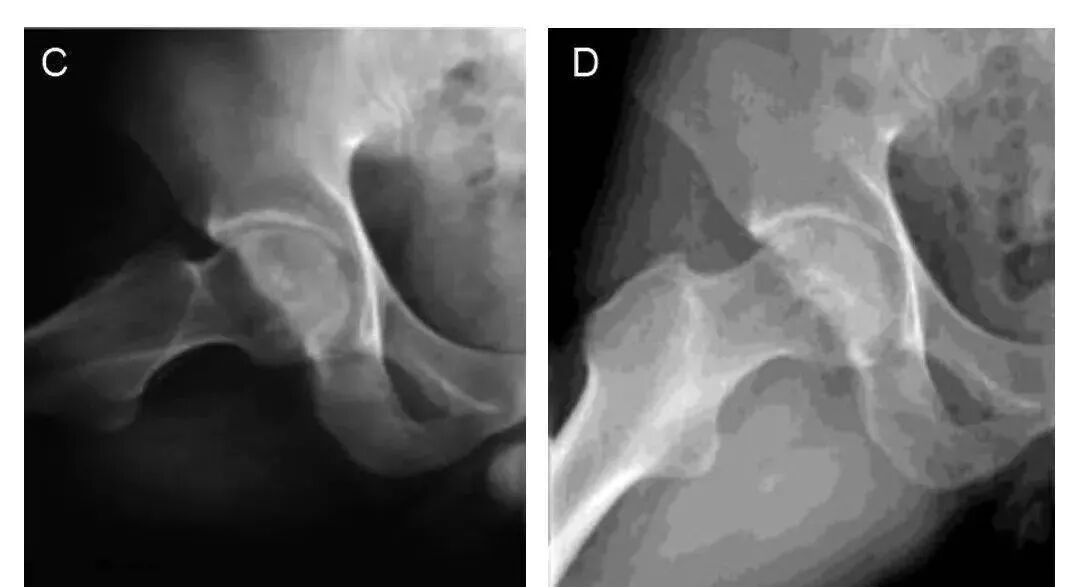

图中A和C:典型病例术前正位和蛙式位X射线片,股骨头内不规则高密度影;

图B和D:典型病例术后7.5年正位和蛙式位X射线片,股骨头外形规整,无塌陷。